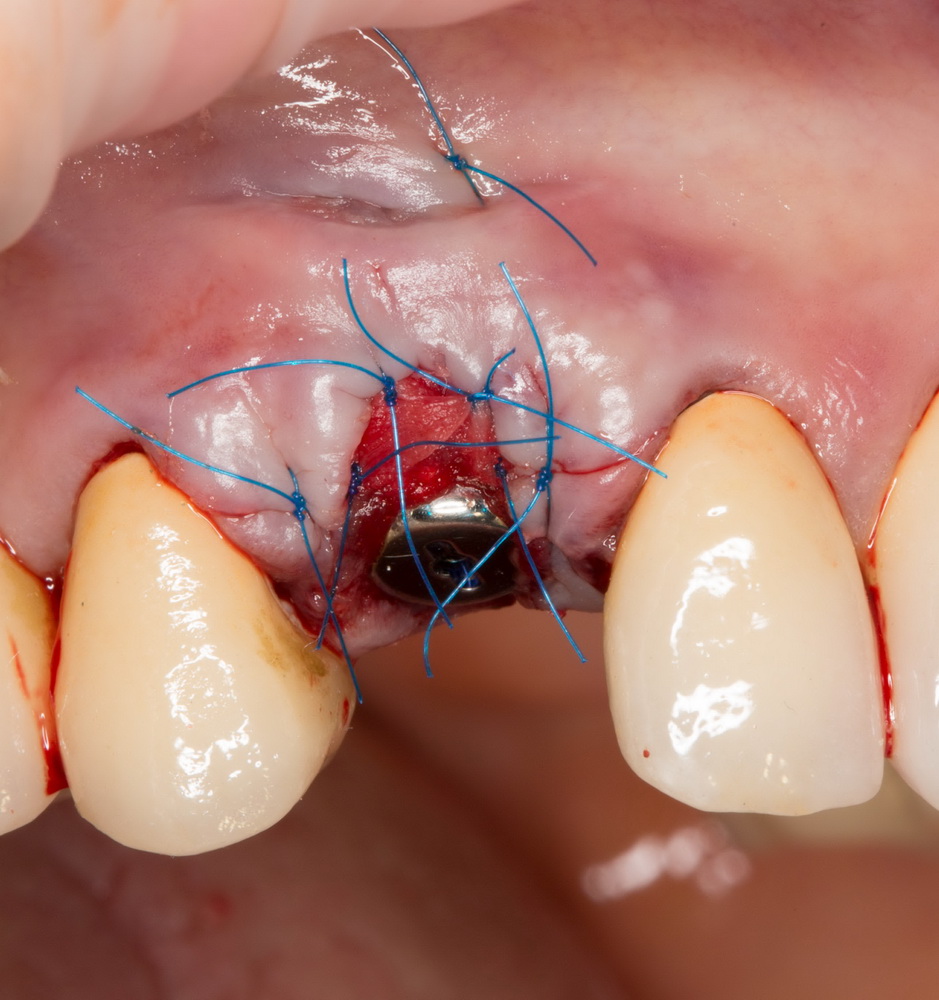

Другой способ понижения травматичности — это, по возможности, объединение нескольких этапов хирургического лечения в одну операцию. Типичный пример — немедленная имплантация: удаление зуба, установка импланта и формирование десны проводятся за один этап:

Можно существенно снизить травматичность хирургического вмешательства, просто уменьшив размер операционной раны. Для этого делается доступ точно по диаметру импланта. Такой подход называют «имплантацией без разрезов», что в корне неверно: